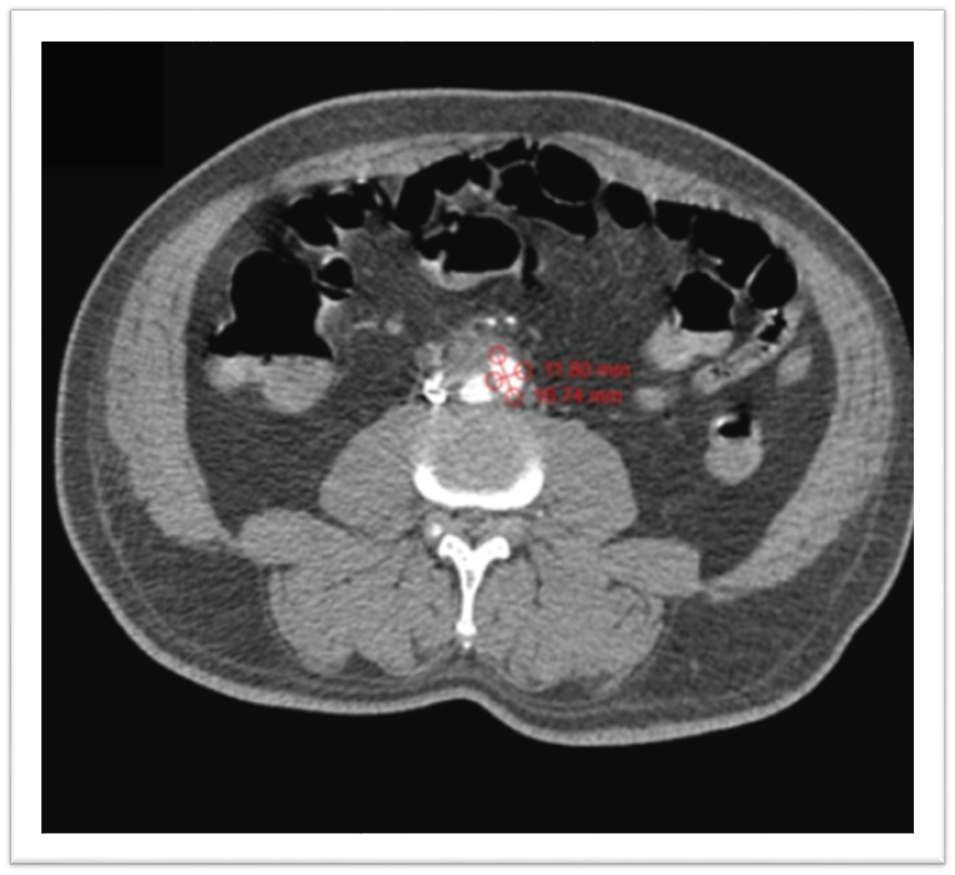

The aneurysmal neck measured 17.5 mm, as shown in [Figure 2]. The residual aortic lumen measures 16.7x11.8mm in AP x TR dimensions. The body of the aneurysm is closely abutting the third and fourth parts of the duodenum, associated with increasing hyperdensity in the duodenal lumen on the arterial and venous phases, suggestive of aortoenteric fistulous communication.

Figure 2. CT Abdomen.